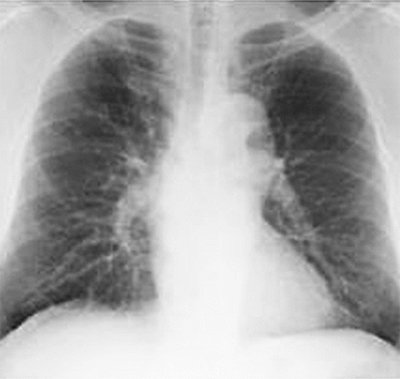

胸部エックス線(レントゲン)写真=写真左=では、肺の約3分の1は近接する臓器(心臓や血管、横隔膜など)と重なるため、小さな肺がんを見つけることが困難となる。一方、CT画像=写真右=は0・5㎜の厚さで横断像を撮影するため、重なりがなく、さらに分解能に優れるため、胸部エックス線には映らないような淡い陰影まで検出できる。「CT検診で発見した肺がんは86%以上が腫瘍3cm未満の早期で、5年生存率も90%と好成績を収めています」と平岩医師は話す。低線量肺がんCT検査料は9260円(税別)。